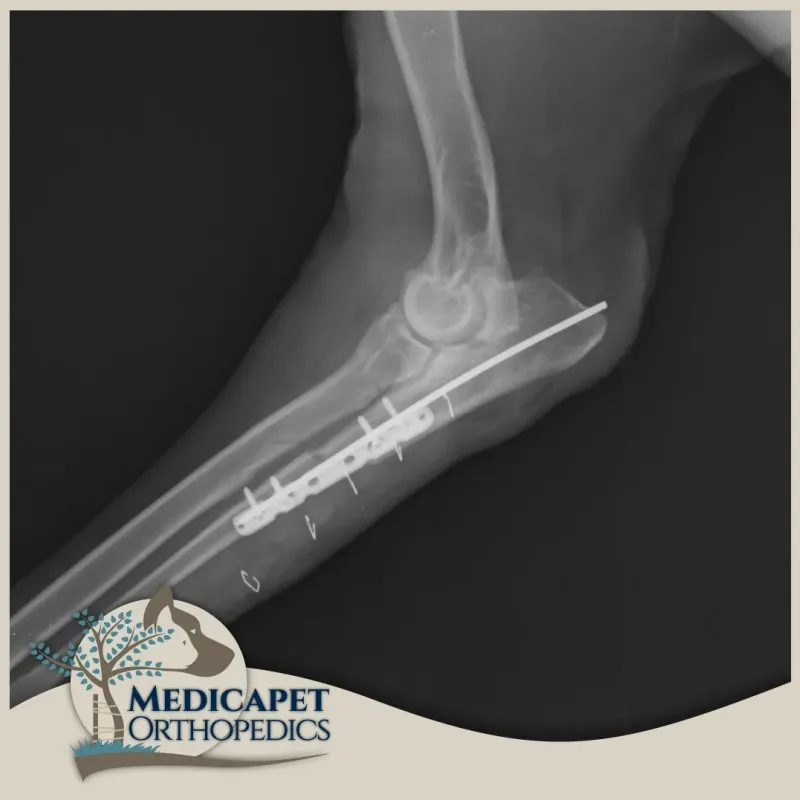

Tedavide cerrahi seçeneklerimizi değerlendiriyoruz. Cerrahi tekniğimize karar verirken displazinin türüne göre hareket etmemiz gerekiyor. Amaç eklemin herhangi bir yerindeki aşırı yükü hafifletmek ya da kaldırmak olduğu için cerrahi tedavi genellikle radius ve ulna kemiklerinde bir takım açısal değişiklikler yapmayı gerektiriyor.

Dirsek displazisi tanısı zor, tedavisi ise profesyonel tekniklere dayanan bir hastalıktır. Bu teknikler milimetrik hassas ölçümlerle uygulamanması gereken tekniklerdir. Bu sebeple sıklıkla BT ya da MRG gibi görüntüleme tekniklerinden faydalanmayı gerektirir.